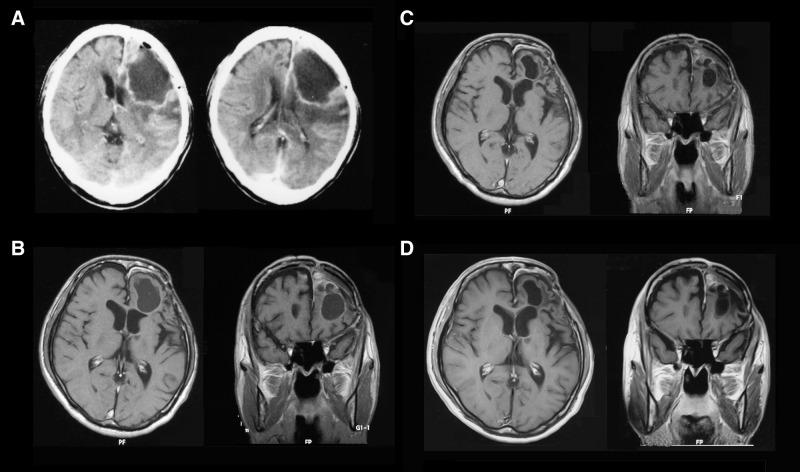

质子治疗是一种放射疗法。在常规的放射治疗中,使用的是被称为光子线的电磁波,如X射线和伽马射线来进行治疗;而在质子线治疗中,则使用一种称为质子线的放射线来进行治疗。

在癌症治疗中,放射治疗是一把双刃剑,这种治疗方式在杀灭癌细胞的同时难免伤及健康组织。而质子治疗的出现,为癌症患者带来了精准治疗选择。

质子疗法与传统放射治疗中使用的 X 射线不同,它利用质子束精确靶向癌细胞。质子直接在肿瘤内的特定深度(称为布拉格峰)释放大部分能量。传统放疗的X射线是一种能量射线,它们进入人体后从另一侧穿出。由于在进入人体时释放的辐射最强,它们可能在抵达肿瘤的路径上损伤健康组织和器官。当这些射线继续穿过人体、经过肿瘤后,也可能对健康组...

质子治疗是当今先进的放射治疗形式之一,能够将高剂量的辐射直接作用于肿瘤,同时保护周围的健康组织。它通过利用布拉格峰发挥作用,在组织的预定深度释放大部分质子能量。这与传统的基于光子的放射治疗形成了鲜明对比,在光子治疗中,辐射会沿着整个射线路径持续释放,不仅损伤癌细胞,也会损害周围的健康细胞。质子可以被控制在特定点(布拉格...